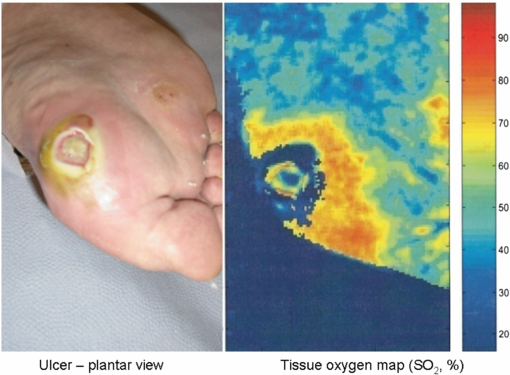

3.3. Photoacoustic tomography